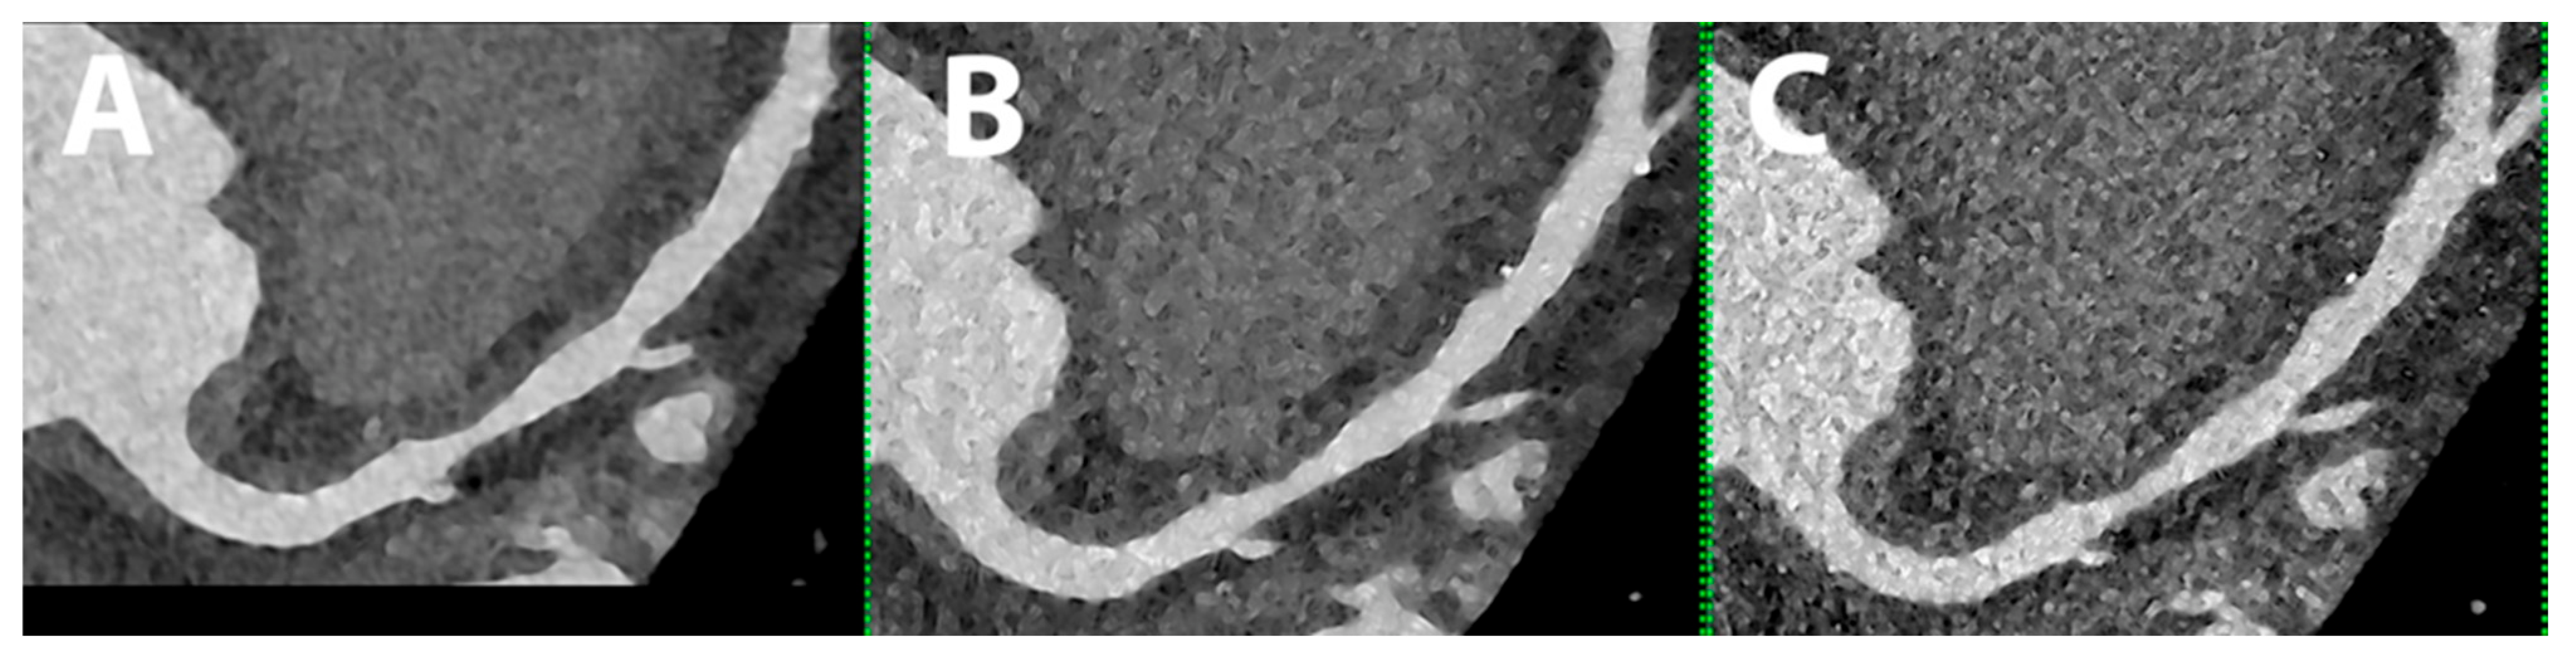

5.9. Reduction in Contrast Media Volume

- Emrich, T.; O’Doherty, J.; Schoepf, U.J.; Suranyi, P.; Aquino, G.; Kloeckner, R.; Halfmann, M.C.; Allmendinger, T.; Schmidt, B.; Flohr, T.; et al. Reduced Iodinated Contrast Media Administration in Coronary CT Angiography on a Clinical Photon-Counting Detector CT System: A Phantom Study Using a Dynamic Circulation Model. Investig. Radiol. 2023, 58, 148–155. [Google Scholar] [CrossRef]

- Cundari, G.; Deilmann, P.; Mergen, V.; Ciric, K.; Eberhard, M.; Jungblut, L.; Alkadhi, H.; Higashigaito, K. Saving Contrast Media in Coronary CT Angiography with Photon-Counting Detector CT. Acad. Radiol. 2023, in press. [Google Scholar] [CrossRef]